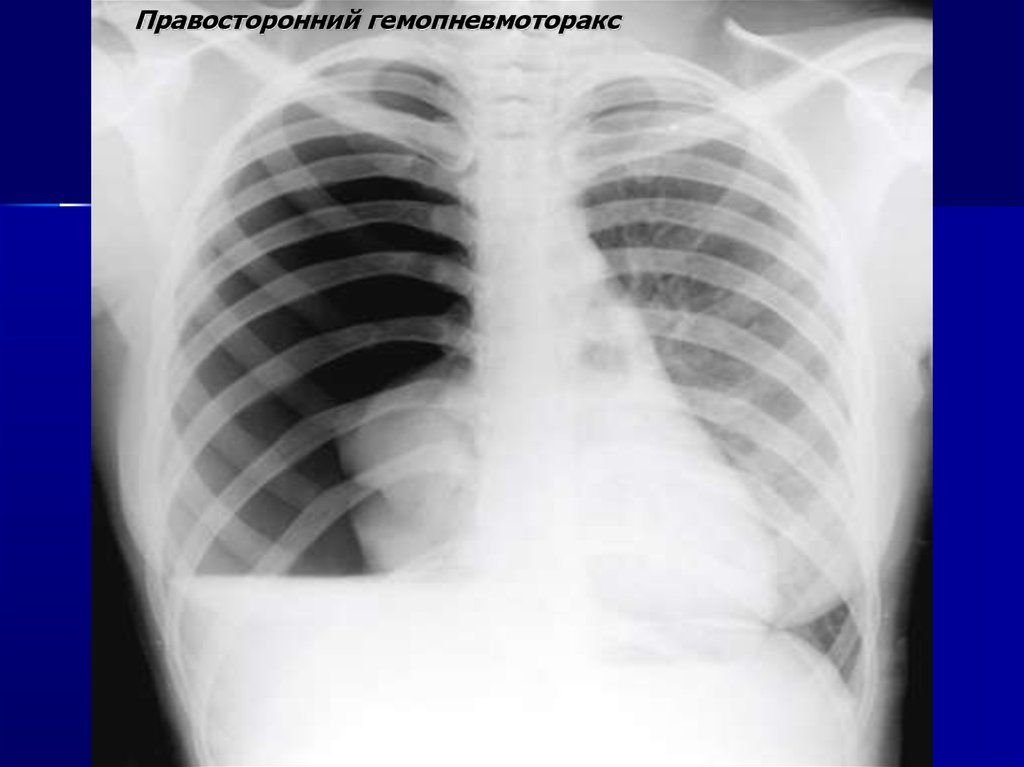

Правосторонний гемопневмоторакс